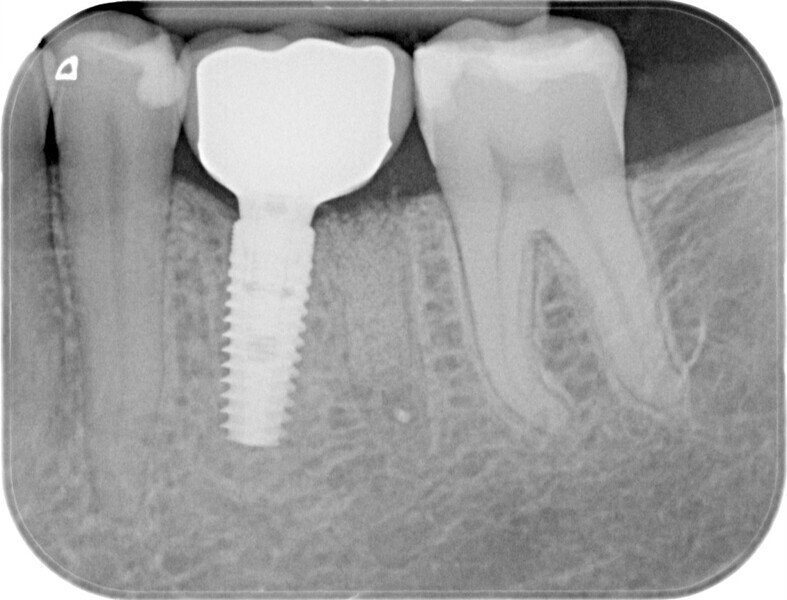

A 39-year-old male patient presented with a deeply fractured mandibular first molar two years after hemisection (Fig. 1). After the patient had opted for an implant-borne solution, an immediate implant placement and restoration with a PMMA provisional crown on a final Atlantis abutment (Dentsply Sirona) was planned.

The implant site was prepared following the recommended drilling protocol for the planned PrimeTaper EV 4.2 mm diameter implant (drills #1, 3 and 4; Fig. 2). After cortical preparation with drill #5, the implant was placed. The preparation was finalised with a tap, owing to dense trabecular bone (Fig. 3). The implant was inserted to a torque of 42 Ncm (Fig. 4).

Immediately after implant placement (Fig. 5), the abutment position was registered with an intra-oral scan using Primescan (Dentsply Sirona; Fig. 6). At the end of the surgical procedure, the socket was grafted with Symbios (Dentsply Sirona) and a healing abutment was seated (Fig. 7). Radiographic evaluation was performed on the same day (Fig. 8). On basis of an intra-oral scan, an Atlantis abutment and Atlantis provisional crown were designed and fabricated with an Atlantis IO FLO (Fig. 9).

During the healing period, the final crown was manufactured based on the Atlantis Core File. Eight weeks after implant placement, the soft tissue had healed well (Figs. 15 & 16) and was ready for the final zirconia crown (Fig. 17). Radiographic evaluation with the final restoration confirmed the successful outcome of the treatment (Fig. 18).